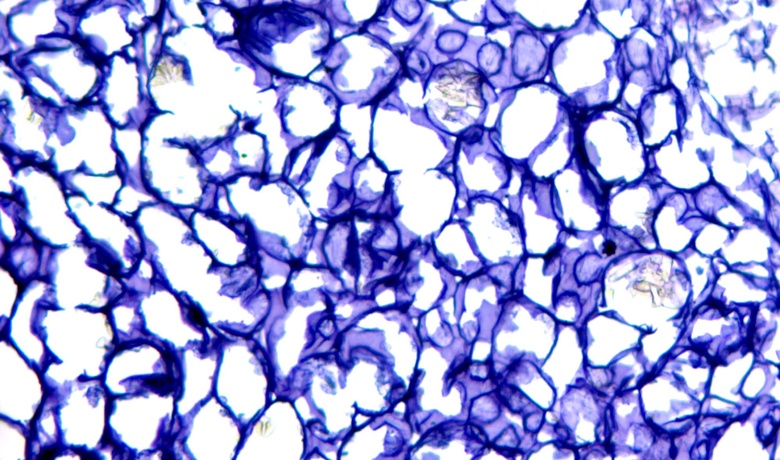

Congo red staining with methanol

Congo red staining is a staining method commonly used for amyloid, which uses the special interaction between Congo red and amyloid to achieve staining. Congo red has a selective affinity for amyloid and can easily stain amyloid. This method has outstanding advantages and can provide clear and accurate dyeing results.

Congo red is an azo dye whose molecule has a long thread-like structure. It binds to amine groups and hydroxyl groups in starchy substances and is attached in parallel to the starch fibers, thus exhibiting a red color. Congo red can be used to identify the decomposition of cellulose or cellulolytic bacteria by dyeing the fiber into a red complex. At the same time, it does not act on cellobiose and glucose.